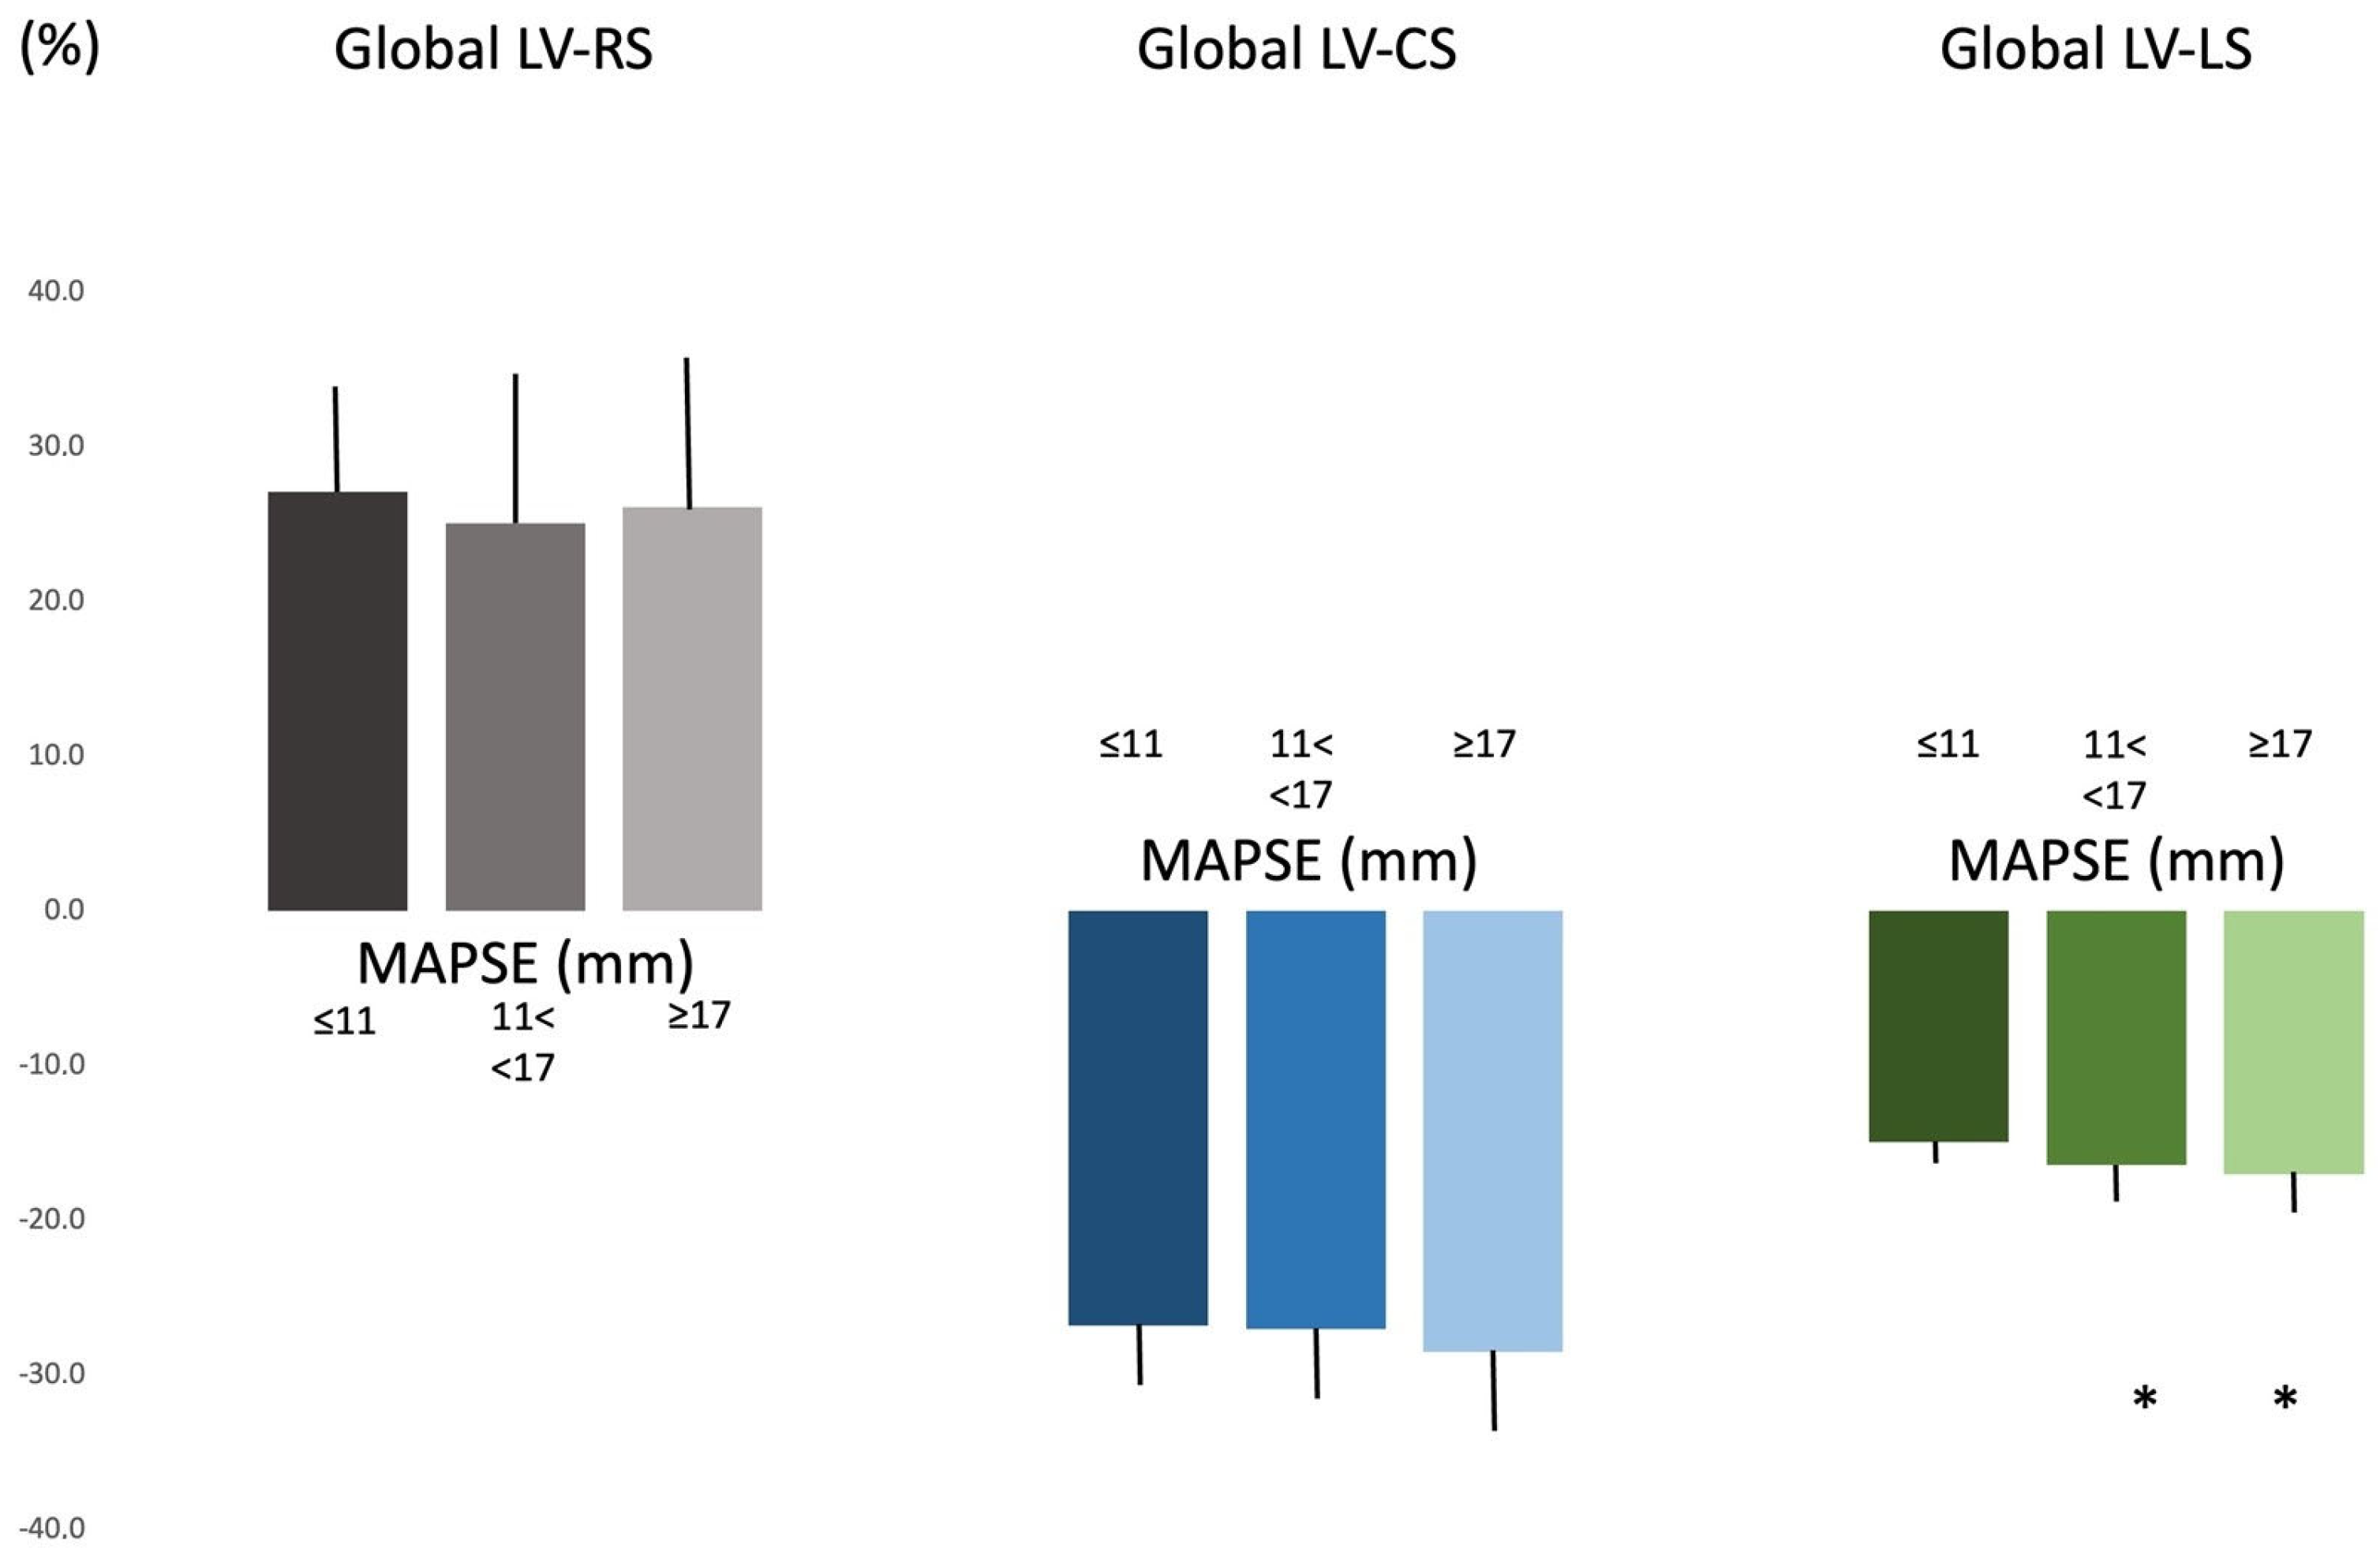

3. Results

| global LV-RS (%) | 25.6 ± 9.9 (24.7) | 27.1 ± 7.1 (28.8) | 25.1 ± 10.3 (24.2) | 26.1 ± 9.9 (23.0) |

| global LV-CS (%) | −27.3 ± 4.8 (−26.6) | −26.8 ± 4.2 (−26.5) | −27.0 ± 4.8 (−26.6) | −28.5 ± 5.2 (−27.0) |

| global LV-LS (%) | −16.3 ± 2.4 (−16.3) | −14.9 ± 1.6 (−14.6) | −16.4 ± 2.3 (−16.3) * | −17.0 ± 2.6 (−17.3) * |